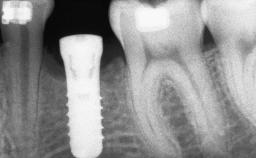

Ridge Preservation and Implant Placement for a Fixed Dental Prosthesis After a Car Accident

It is well known to clinicians that any removal of teeth will, over time, cause the dimensions of the alveolar ridge to be reduced by resorption of the bundle bone and by changes related to external modeling. This development is particularly evident in the crestal region with its thin buccal bone that consists of bundle bone almost entirely. The facial bone will rapidly resorb as blood supply from the periodontal ligament gets disrupted (Araújo and Lindhe 2005). There is no reason why traumatic tooth loss should not have the same consequences. It takes more than achieving implant osseointegration for a treatment outcome to be considered successful. No deficiency of bone or soft tissue is acceptable when an ideal esthetic outcome is the goal. Several articles (Sanz and coworkers 2011; Vignoletti and coworkers 2011) have reported on techniques of improving the alveolar ridge for implant treatment, notably focusing on protecting tissues from resorption.

Bone Augmentation Horizontal|Simultaneous|Sinus Floor Elevation|Staged